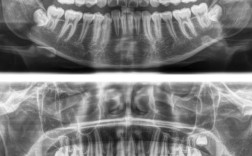

X线片

- 全景片(曲面断层片):观察全口牙根形态、位置,有无根吸收、囊肿、多生牙、阻生牙,牙槽骨高度(判断牙周支持情况)。